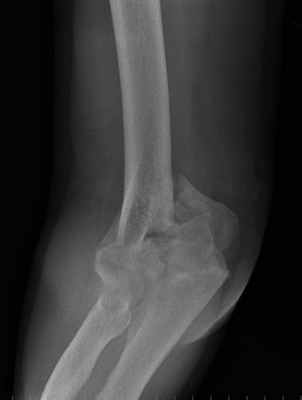

Пациентка с тяжелым внутрисуставным переломом нижнего отдела (мыщелков) плечевой кости с тяжелым повреждением локтевого сустава.

Рентгенограмма до операции.

Выполнена операция: металлоостеосинтез плечевой кости современными пластинами LCP, анатомия локтевого сустава полностью восстановлена.

Гипсовая повязка после операции не применялась, сразу разрешена разработка движений в суставах конечности. Результат через 5 дней после операции. Швы еще не сняты, виден отек, кровоподтеки на конечности после перелома. Уже видна хорошая функция конечности.

Результат через 3 мес. после операции. Функция конечности полностью восстановлена.